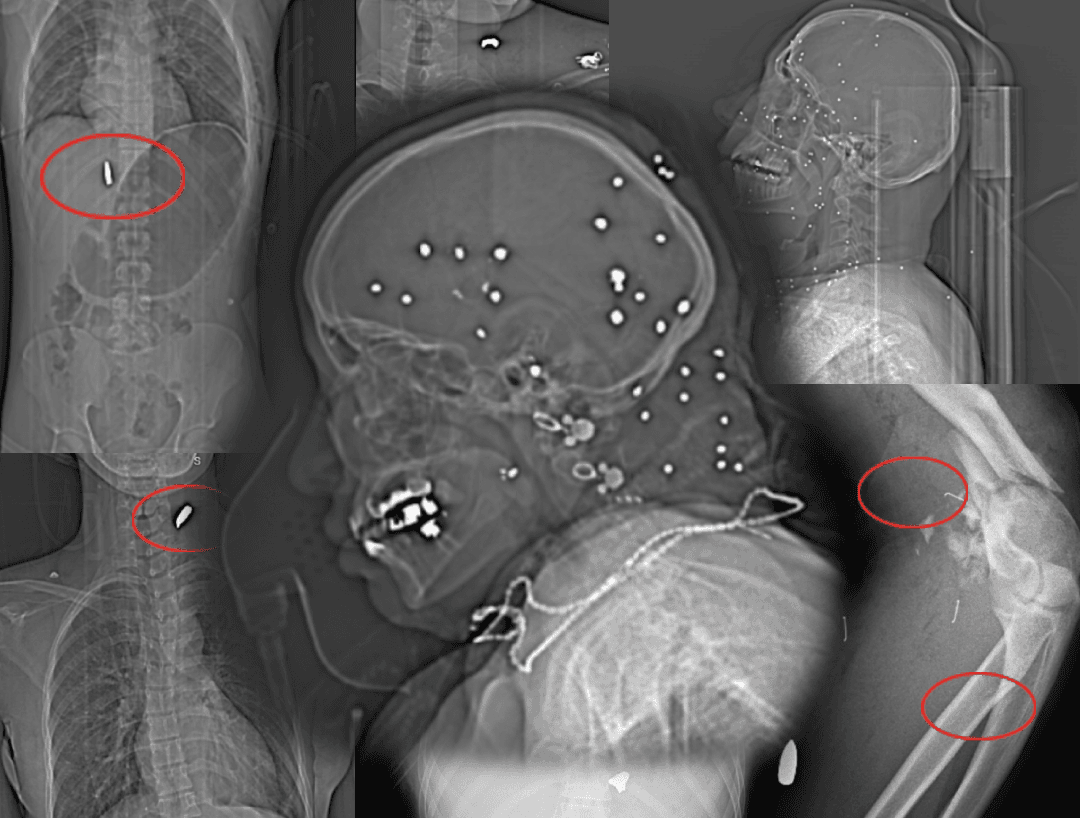

This joint investigation by Factnameh and The Guardian is built around 78 medical images—X-rays, CT scans, and CT angiography—taken from 64 injured people treated at a single hospital in a major Iranian city on 8th and 9th of January. The images were independently verified and reviewed by emergency physicians and a ballistics expert.

Of the 64 cases, 59 showed clear radiological evidence of gunshot or shotgun pellet injuries and were included in the final analysis. Five were excluded due to lack of definitive projectile evidence.

Across the 59 confirmed cases, there were 69 distinct anatomical injury events, since some individuals were hit in more than one body part.

The distribution shows a striking pattern:

3. Abdomen, pelvis, and genital region

Pelvic fractures, embedded metal fragments, and soft tissue destruction were documented. Doctors noted possible injuries to the bladder, intestines, and reproductive organs—raising risks of long-term consequences such as infertility, incontinence, or sexual dysfunction.

In severe pelvic and femur fractures, physicians warned of possible damage to major blood vessels, including the femoral artery, with life-threatening bleeding.

Four cases of pelvic, thigh, and hip injuries: in three images, multiple shotgun pellets are scattered through the soft tissue around the pelvis and thigh, and in one image, there is severe destruction with a comminuted fracture of the femur accompanied b